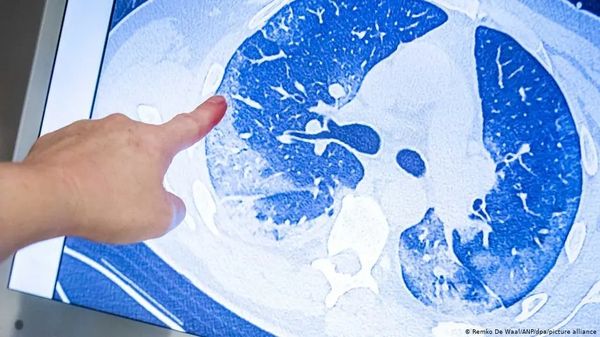

每次随访时,患者都接受了详细的面谈、体检和6分钟的步行测试,也回答了各种问卷,反映他们呼吸困难的情况、生活质量、出院后就医情况等等。研究人员在6个月时随机抽样病人做了肺功能检查和胸部CT,根据需要12个月时又有复查。

曹彬团队此前已在《柳叶刀》(2021年1月)发表过同一批病人6个月时的随访,当时他们发现大约四分之三的新冠幸存者出院后仍有持续的症状,住院期间病情危重的患者,比疾病严重程度较低的患者更可能有肺部气体弥散障碍和影像学异常。